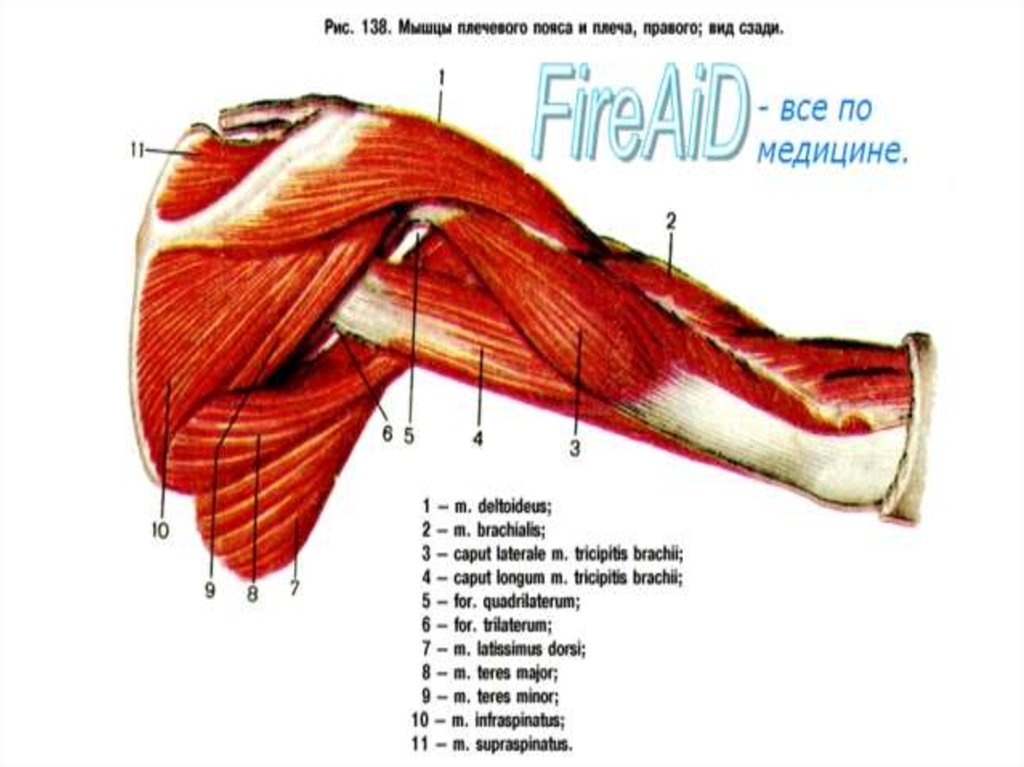

Фотографии поддельтовидной мышцы плечевого сустава

Раздел: Образы вокруг